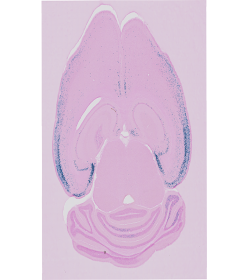

How can I identify brain regions in my images?

By using QuickNII, you will be able to register this image series to the mouse reference atlas version of your choice and obtain adapted atlas maps and coordinates. Further, in-plane non-linear adjustments can be made with VisuAlign in order to obtain a more precise registration.